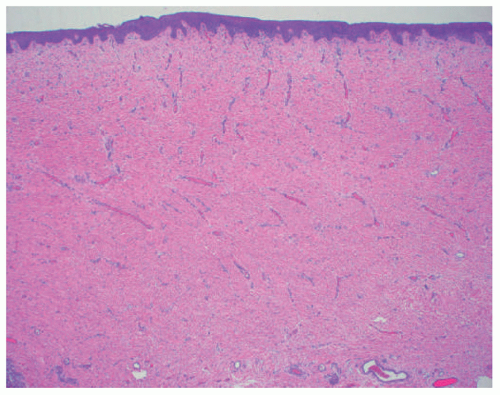

epidermis overlies an edematous dermis with very loose connective tissue.

![]() FIGURE 9-5. Aplasia cutis congenital. Thin epidermis overlies a dermal scar that lacks adnexal structures.